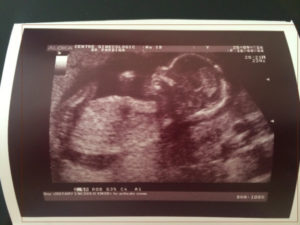

Живот будущей мамы на четвертом месяце заметно увеличивается и округляется – даже под несколькими слоями одежды ее положение не вызывает сомнений у окружающих. Это означает, что плод благополучно растет и начинает набирать подкожный жир, необходимый ему для правильного теплообмена после родов.

- Тело полностью оформлено – его туловище имеет пропорции, приближенные к пропорциям новорожденного.

- Черты лица тоже сформированы: ушные раковины имеют правильные очертания, глаза приобретают способность открываться благодаря тому, что кожа век разделилась.

- Глазные яблоки способны различать свет и тень, поэтому режим плода постепенно будет приспосабливаться к режиму матери – совсем скоро ночью он будет больше спать, а днем – бодрствовать.

- На теле уже присутствует волосяной покров – голова и туловище покрыты пушковым волосом, на веках появились ресницы, над глазными впадинами наметились брови. Кончики пальцев покрыты тончайшей ногтевой пластиной.

- Кожа ребенка на 16 неделе красного цвета и покрыта плотной белой смазкой, которая защищает ее от воздействия околоплодных вод.